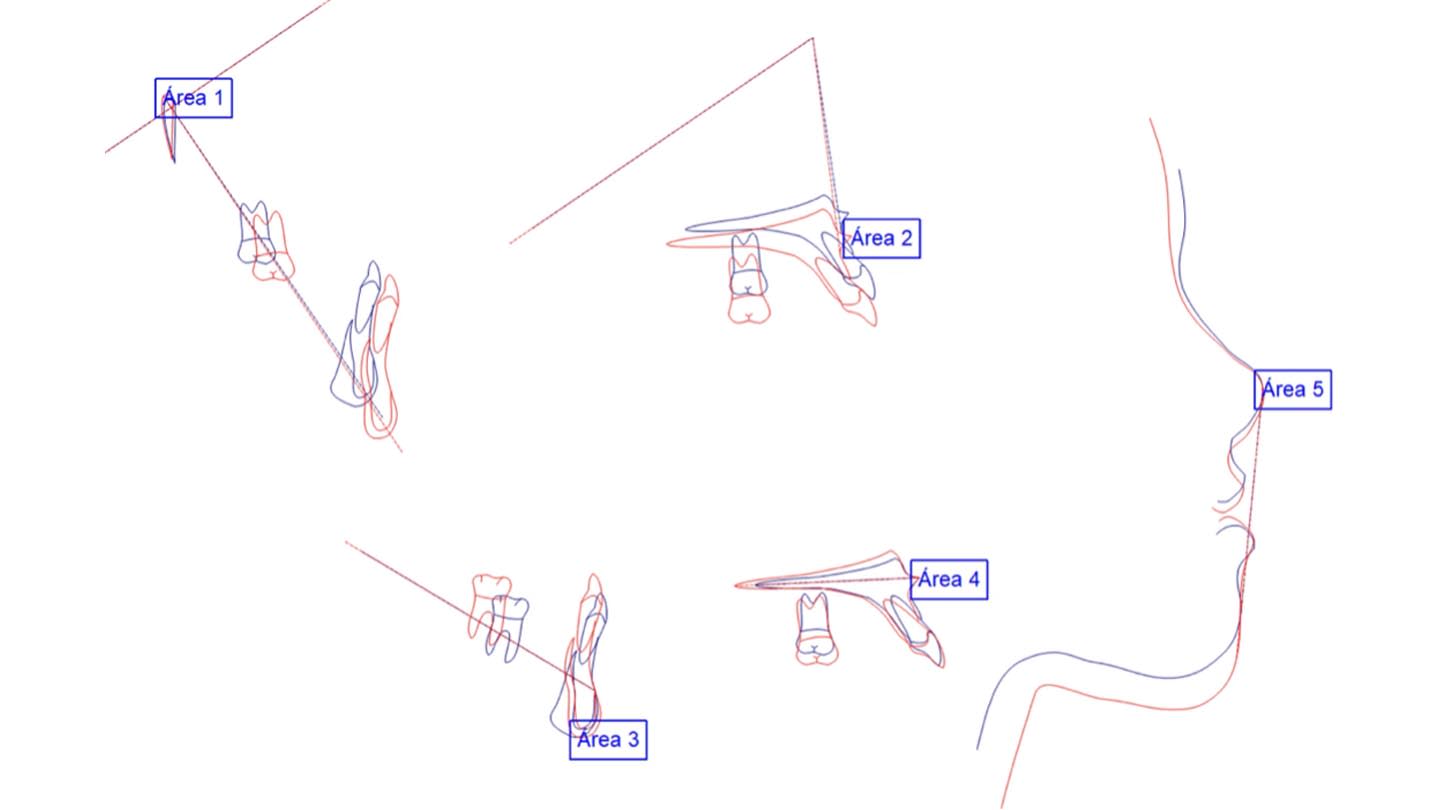

Despite variability in appliance design, all studies reported favorable outcomes with skeletal expanders for addressing transverse deficiencies in young adults. A case presentation illustrating treatment in a 16-year-old patient is shown in Figure 2 through Figure 39. (An additional case presentation may be viewed at compendiumlive.com/go/cced2110.) The studies also agree on the importance of individualizing miniscrew length and diameter in each case.25,26,30-32,34